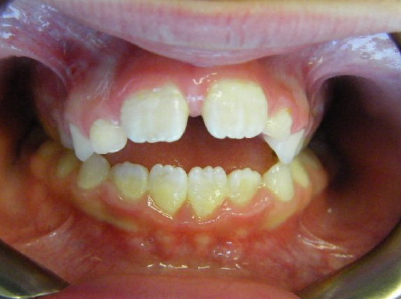

Early Phase of Treatment Examples

Patient 1: Thumb sucking and crowding of the upper front teeth.